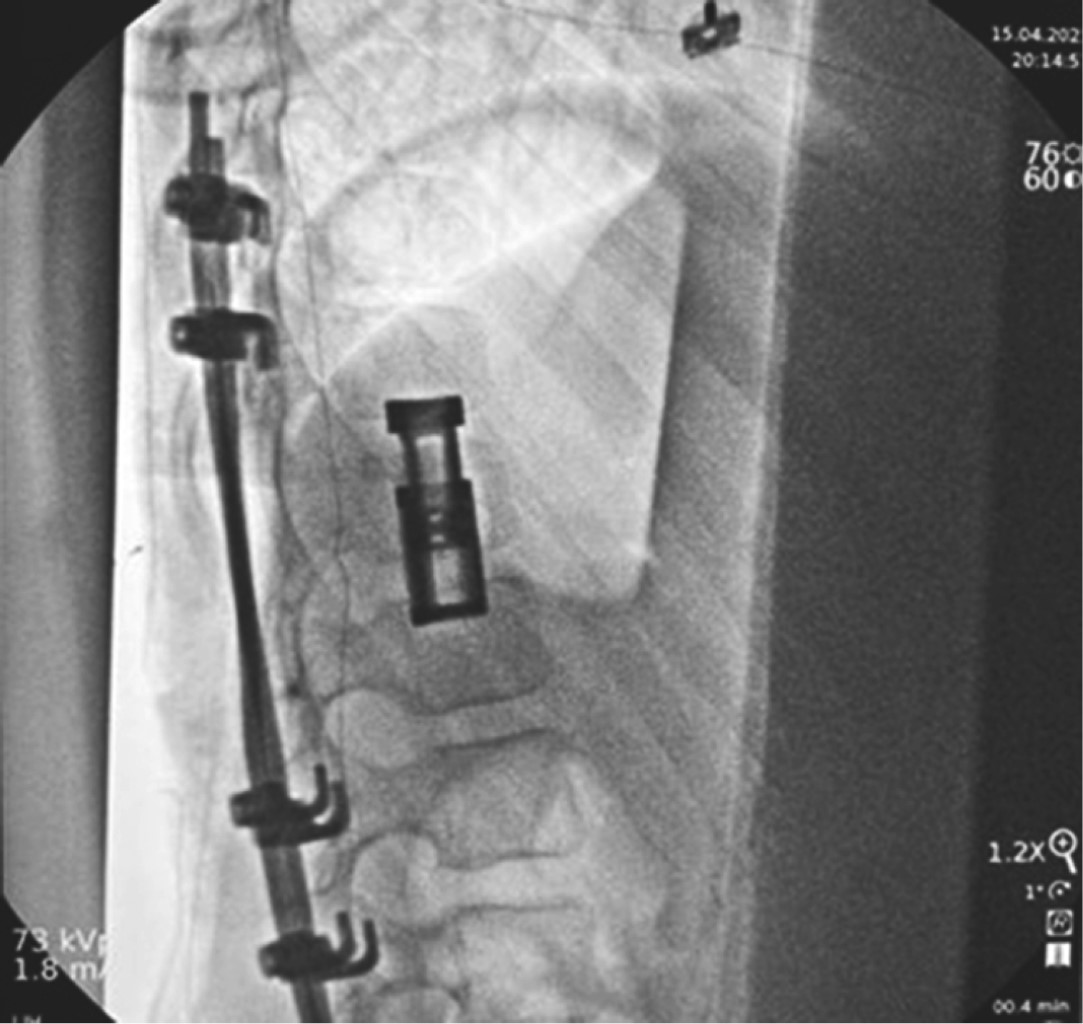

Es intervenida quirúrgicamente mediante una costotransversectomía izquierda, corpectomía T12 y resección de lesión. Para la instrumentación se movilizó la raíz izquierda T11 en sentido superolateral y la de T12 inferolateral aproximadamente 3 cm, observando el saco dural, creando de esta forma un corredor interneural. Se insertó la caja rellenada de matriz ósea de forma colapsada a través del corredor y una vez que pasa ambas raíces, es rotada para colocar la caja en alineación con el eje longitudinal de la columna. La porción telescópica de la caja es colocada caudalmente evitando el estiramiento de la raíz nerviosa inferior a medida que se expande. Posteriormente se realizó la fijación de T10-L2 con ganchos sublaminares. Como hallazgos transquirúrgicos se observaron cavidades llenas de sangre de aspecto antiguo, color café rojizo, múltiples tabiques en su interior que se extendía desde la lámina, pedículo y cuerpo vertebral con invasión al canal medular condicionando su compresión sin datos de afección a la duramadre.